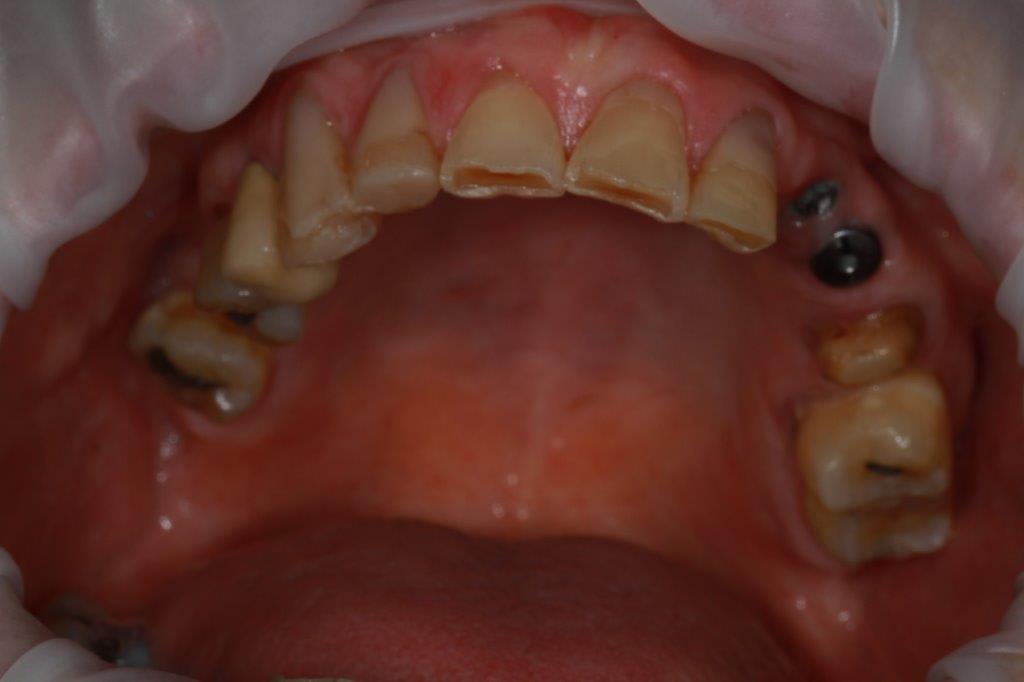

petit cas sympa ancien bridge très mobile....plutôt que d'extraire 25, j'ai déposé la couronne, retraité la dent stabilisation pendant deux mois puis séance d'ostéotension et ce jour pose de deux axioms PX 34120 après expansion...

Pxav, je vois des zones concaves entre les implants et en mesiale, tu laisses les expanseurs pour visser les implants, tu réalises 4 points d'impacte avec les demi-lunes ?

comme je n'ai pas fait de décharges osseuse en vestibulaire, j'ai effectivement travaillé toute la longueur de la crête, mais, là j'ai ôtè les expanseurs avant de visser les implants car ce sont des PX qui ont un apex assez fin, pour des regular j'aurais pratiqué différemment.

par contre je suis passé par le stade implants lisse (34100 et 34120)

par contre les axioms doivent être posé en sous crestal, ce qui est fait ici, avec sans doute comme souvent une nécessitè d’ostéotomie, lors de la mise en charge, car il est fréquent que le col implantaire soit recouvert.